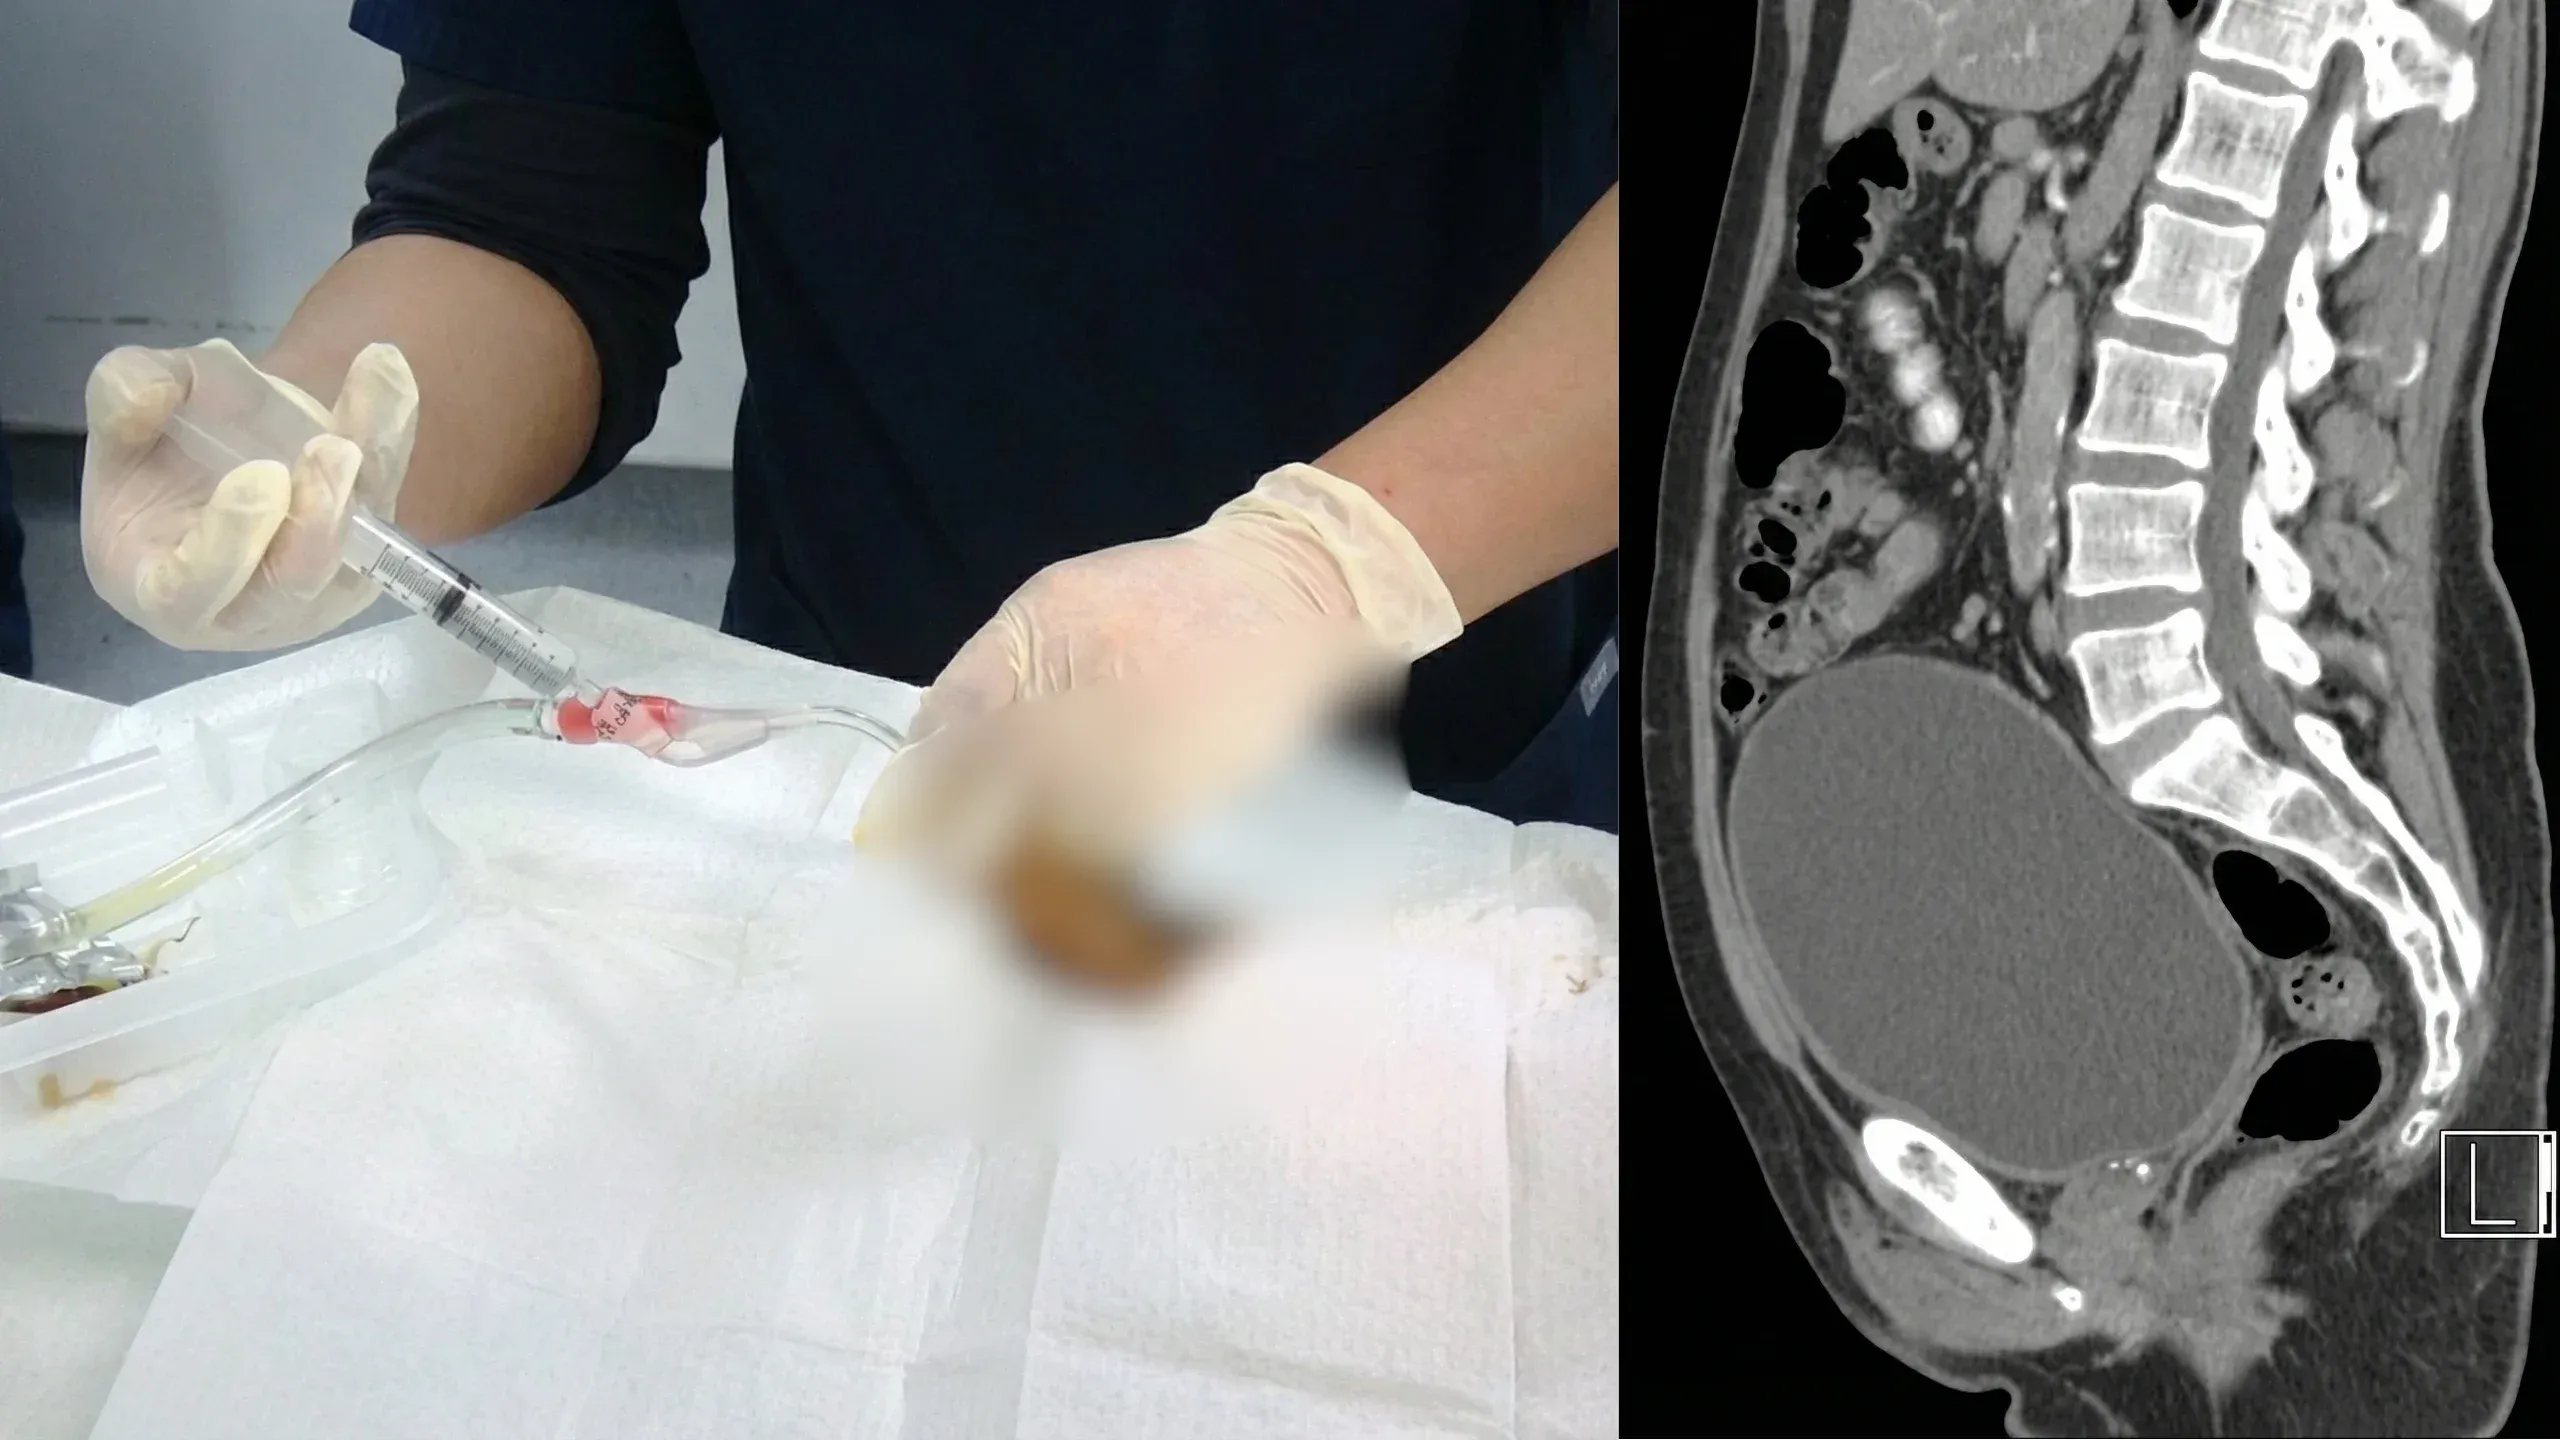

השלפוחית שלי החזיקה 900 מ״ל של שתן

זה היה יום שלישי במאי. בערך בשתיים וחצי לפנות בוקר.

התעוררתי עם הלחץ המוכר. הדחף להשתין. שום דבר חריג, בשלב הזה כבר קמתי לפחות שלוש פעמים בלילה.

חצי ישן, גררתי את עצמי לשירותים. עמדתי מול האסלה.

וחיכיתי.

כלום.

התאמצתי קצת. נרגעתי. ניסיתי שוב.

התיישבתי, זה בדרך כלל עזר.

עדיין כלום.

דקה הפכה לחמש. חמש הפכו לעשר.

ואז התחיל הכאב.

לא אי־נוחות רגילה. זה היה שונה. לחץ שהלך ונבנה בבטן התחתונה, כאילו משהו עומד להתפוצץ.

הסתכלתי למטה וראיתי שהבטן שלי נפוחה, מתוחה באופן נראה לעין, משלפוחית שלא מצליחה להתרוקן.

התחלתי להזיע.

חמש עשרה דקות כבר. עדיין כלום. הכאב החמיר.

קראתי לאשתי. ‘יעל, משהו לא בסדר.’

היא מצאה אותי כפוף, נאחז בקיר. לא הצלחתי אפילו לעמוד זקוף.

“צריך לנסוע לבית חולים,” היא אמרה.

לא התווכחתי.

הנסיעה למיון לקחה 15 דקות. זה הרגיש כמו שעה.

זה הרגיש כאילו השלפוחית שלי יכולה להתפוצץ בכל רגע. כל מהמורה בכביש שלחה גל כאב דרך האגן שלי. נאנקתי. גנחתי. הוצאתי קולות שלא ידעתי שגבר מבוגר מסוגל להוציא.

גבר בן 63, מתייפח כמו ילד.

בבית החולים הכניסו אותי מיד. האחות השתמשה במונח שהכרתי רק מהפחדים הכי גרועים שלי:

“אצירת שתן חריפה.”

השלפוחית שלי הכילה יותר מ־900 מ״ל שתן. כמעט ליטר שלם. וזה לא יצא לבד.

היו חייבים להחדיר צנתר.

אם אף פעם לא עברת את זה, אני מקווה שלעולם לא תעבור.

צינור דק שמוכנס דרך השופכה, עד לשלפוחית.

זה לא הכאב, משתמשים בג׳ל מאלחש.

זו ההשפלה.

חוסר האונים של לשכב על מיטה בזמן שזר מוחדר צינור לאזור הכי פרטי בגוף שלך.

בזמן שאשתי יושבת בפינה, מסתכלת, והדמעות זולגות על פניה.

כשהשתן סוף סוף התחיל לזרום, ההקלה הייתה מיידית. הלחץ ירד. הכאב נעלם.